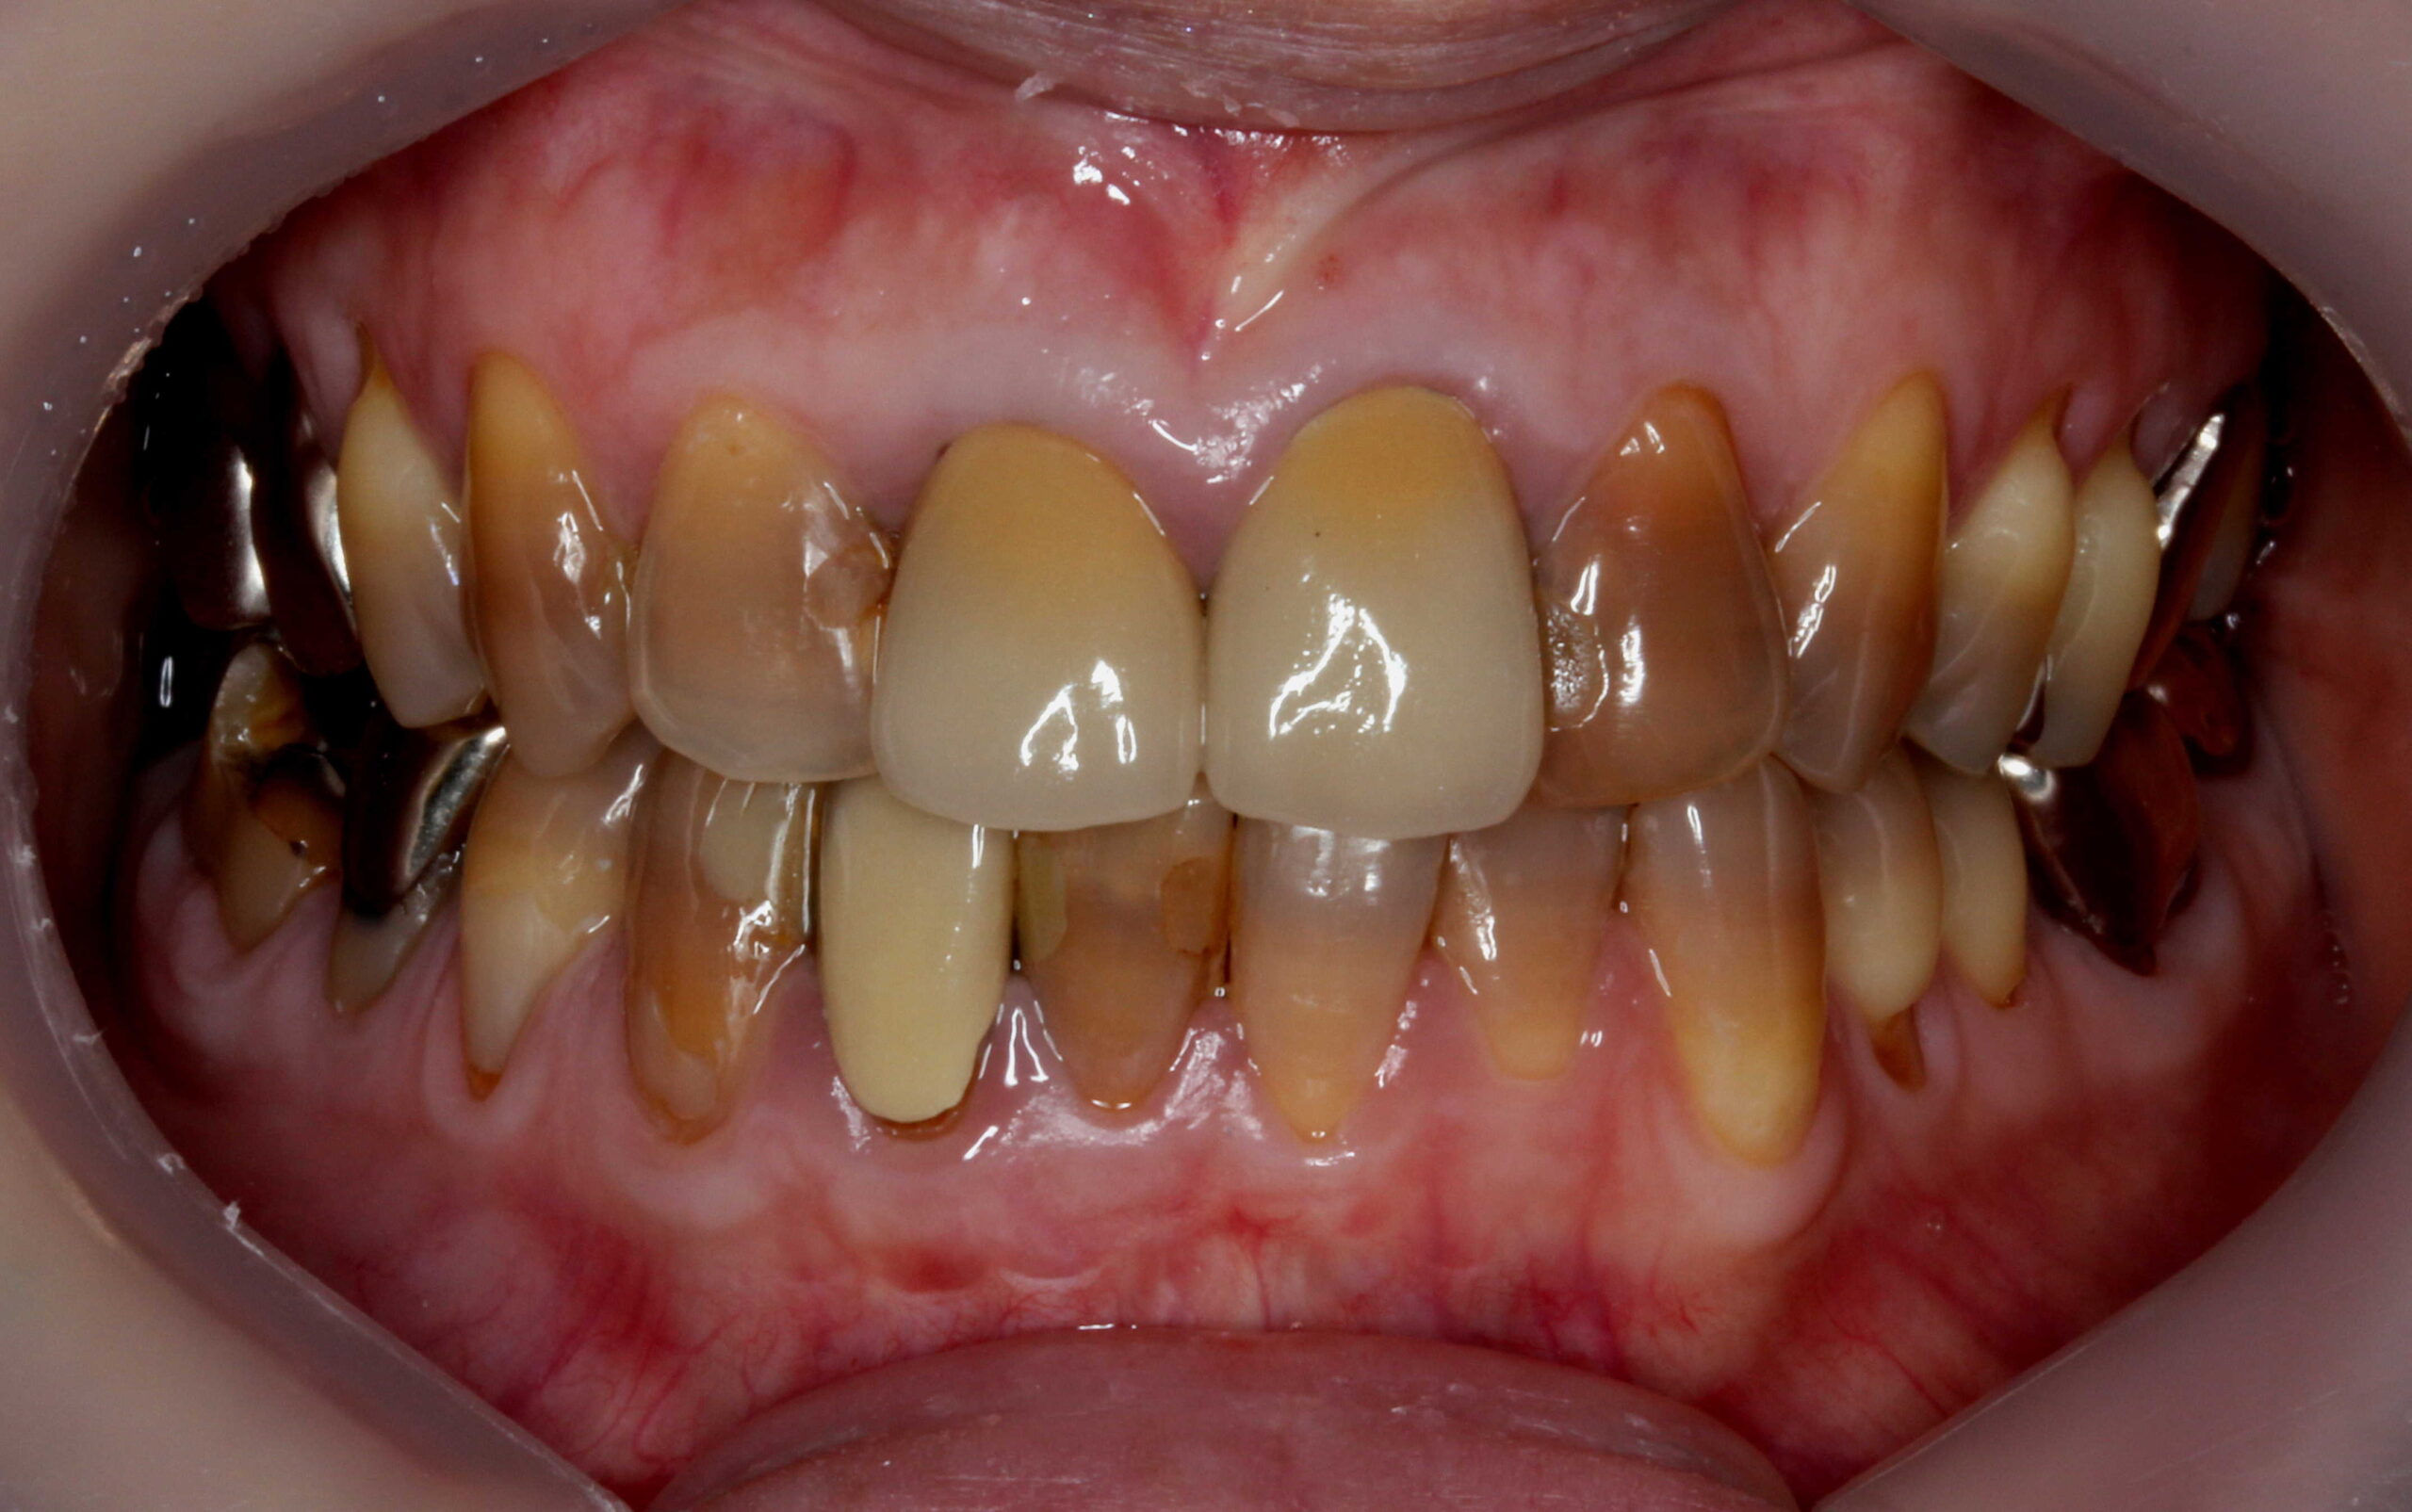

テトラサイクリン歯でホワイトニングをした事例

テトラサイクリン歯に対してもホワイトニングは一定の効果があります。

ホワイトニング前 ホワイトニング後

当院のホワイトニングは高品質で効果が高い製品なのですが、完全な白い歯にすることは難しいです。

削らないラミネートベニアは歯を削らないセラミックの審美歯科です。

なお、左上3は他院で治療中のため、歯のマニキュアのみ行っています。

非常に透過性がある材料なので、元の歯(支台の歯)の色味が透けます。(透過性のないベニアも製作出来ますが、透明感がないので色味が白浮きして不自然になります。)

元々の歯をホワイトニングで白くキレイにした上で、透過性のあるベニアを貼るのが一番自然な仕上がりになります。